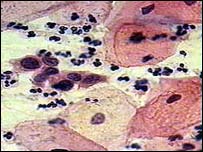

گردن رحم يا زهدان(Cervix) قسمتی از دستگاه تناسلی زن است و ناحيه باريک و تحتانی رحم را که به مهبل باز می شود شامل می شود. سرطان گردن رحم نوعی بيماری است که در آن رشد بافت بدخيم از ناحيه گردن رحم نشات می گيرد و به طور نامنظم و فزايندهای تکثير و منجر به تراريختگی آن می شود. سرطان گردن رحم دومين سرطان شايع دستگاه تناسلی زنان و پنجمين سرطان بعد از سرطان های ريه، پستان، روده و جسم رحم در سراسر جهان است که حدود % ۶ کل سرطان زنان را تشکيل می دهد. با توجه به سلولی که دچار تراريختی و سرطان شده است اشکال مختلفی از سرطان گردن رحم وجود دارد که هر کدام نشانه ها و عوارض خاص خود را دارند. شايع ترين اشکال سرطان گردن رحم عبارتند از: i) سرطان بافت بشره ای يا سنگفرشی (Squamous cell carcinoma)- اين سرطان از شا يع ترين انواع سرطان گردن رحم است که حدود %۷۵ اشکال سرطان گردن رحم را تشکيل می دهد. اين سرطان از ياختههای مفروش لايه سطحی گردن رحم شروع میشود و رشد نسبتاً آهستهای دارد و اغلب ماهها بلکه سالها طول می کشد تا به بافتهای اندام های مجاور سرايت کند. بيشتر مبتلايان اين نوع سرطان، زنان ۴۰ تا ۶۰ سال هستند. ii) سرطان غدد مترشحه مخاطی ( Adenocarcinoma) – اين نوع سرطان گردن رحم معمولاً در زير بافت پوششی گردن رحم رشد می کند و معمولاً بين سنين ۲۵ تا ۴۰ سالگی ديده می شود. همه انواع تغييرات ياختههای گردن رحم بدخيم (سرطانی ) نيستند. در زنانی که ياختههای گردن رحم آنها دچار تغييرات غير سرطانی شدهاند اغلب نتيجه عفونت و يا تورم آن است که در اصطلاح آسيب شناسی به آن ديسپلازی (Dysplasia) گفته می شود. ديسپلازی گردن رحم سرطان نيست اما اطلاعات بالينی و آماری آن را عامل مقدماتی برای سرطانی شدن گردن رحم تلقی میکنند. اين تغييرات اغلب در سنين ۲۵ تا ۳۵ سالگی تظاهر میکند. ياختههای ديسپلازی گردن رحم از نظر شکل در زير ميکروسکوپ شبيه ياختههای سرطانی هستند ولی مانند ياختههای سرطانی مهاجم نيستند و به بافتهای مجاور آسيبی نمی رسانند. علائم هشدار دهنده سرطان گردن رحم • درمراحل ابتدايی هيچ نشانه ای ندارد در شرايطی که سرطان گردن رحم مهاجم و به ديگر اندامها گسترش يافته باشد علاوه بر نشانه های فوق علائمی مانند يبوست، مشاهده خون در ادرار، گرفتگی مجرای ادرار، باز شدن غير طبيعی گردن رحم و کم خونی تظاهر می کند.

• آزمايش پاپ اسمير (Papanicolaou Smear)- الگوی غربالگری سرطان گردن رحم جهت تشخيص پيدايش ياختههای پيش سرطانی و سرطانی، رديابی انواع عفونتهای ناشی از باکتری، قارچ و ويروس در نواحی گردن رحم و مهبل است. آزمايش پاپ اسمير پس ازشروع فعاليت جنسی سالی يک بار و پس از دو تست منفی هر ۳ سال يک بار تکرار میشود. اين آزمايش معمولاً دو هفته پس از اتمام عادت ماهانه و حداقل ۴۸ ساعت پس از مقاربت جنسی توصيه میشود. پس از نتيجه مثبت آزمايش پاپ اسمير و مشاهده ناهنجاری ياخته های گردن رحم، اقدام بعدی بررسی کولپوسکوپی (Colposcopy) گردن رحم است که بزرگنمايی 8 تا 40 برابر ياخته را امکانپذير می کند. • نمونه برداری يا بيوپسی (biopsy)- بررسی ميکروسکوپی از نمونه بافت تومور است. اين آزمايش بسيار مهم است زيرا مطمئن ترين روش برای تشخيص سرطان گردن رحم و نوع آن به حساب می آيد. • آزمايش شيلر(Schiller test)- در اين روش ابتدا اسيد استيک رقيق به روی ياختهها ماليده میشود و سپس محلول يد روی آنها ريخته می شود. سپس توسط ابزاری به نام کولپوسکوپ که مجهز به بزرگنما است ياختههای گردن رحم مورد بررسی بصری قرار می گيرند.در اين روش ياختههای سالم گردن رحم به رنگ قهوهای ديده می شود، در حالی که ياختههای تراريخته به رنگ سفيد يا زرد نمايان میشود. اين روش کاملاً بدون درد است و هيچ عوارض جانبی بر جا نمی گذارد. اشکال مهاجم گردن رحم با بررسی بالينی مثانه، راست روده، تخمدان، جسم رحم، مهبل و آزمايش ياختههای گردن رحم تشخيص داده می شود. پس از تشخيص اوليه سرطان گردن رحم، آزمايشات تکميلی ديگری مانند آزمايش خون، ادرار، راديوگرافی قفسه سينه ، سی تی اسکن، کت اسکن، ام آر آی، سونوگرافی مهبل، راديوگرافی لگنچه کليه از طريق تزريق ماده حاجب (intravenous pyelography) برای بررسی دامنه گسترش سرطان به ديگر اندامها بکار گرفته می شود. الگوهای درمانی سرطان گردن رحم الگوهای درمانی بيماری سرطان گردن رحم بستگی به نوع سرطان، وضعيت بيماری در شروع درمان، سن، وضعيت سلامت عمومی و چگونگی واکنش بيمار به نوع درمان دارد. با توجه به سن و وضعيت سلامت بيمار ممکن است يک يا ترکيبی از الگوهای درمانی زير بکار گرفته شود: ۱- جراحی – الگوی درمانی محل ضايعه است و با توجه به وضعيت و دامنه گسترش ضايعه اعمال میشود. در شرايطی که سرطان هنوز محدود به ناحيه گردن رحم باشد و بيمار تمايل به تشکيل خانواده داشته باشد تنها ناحيه تراريخته گردن رحم با عمل جراحی برداشته میشود.